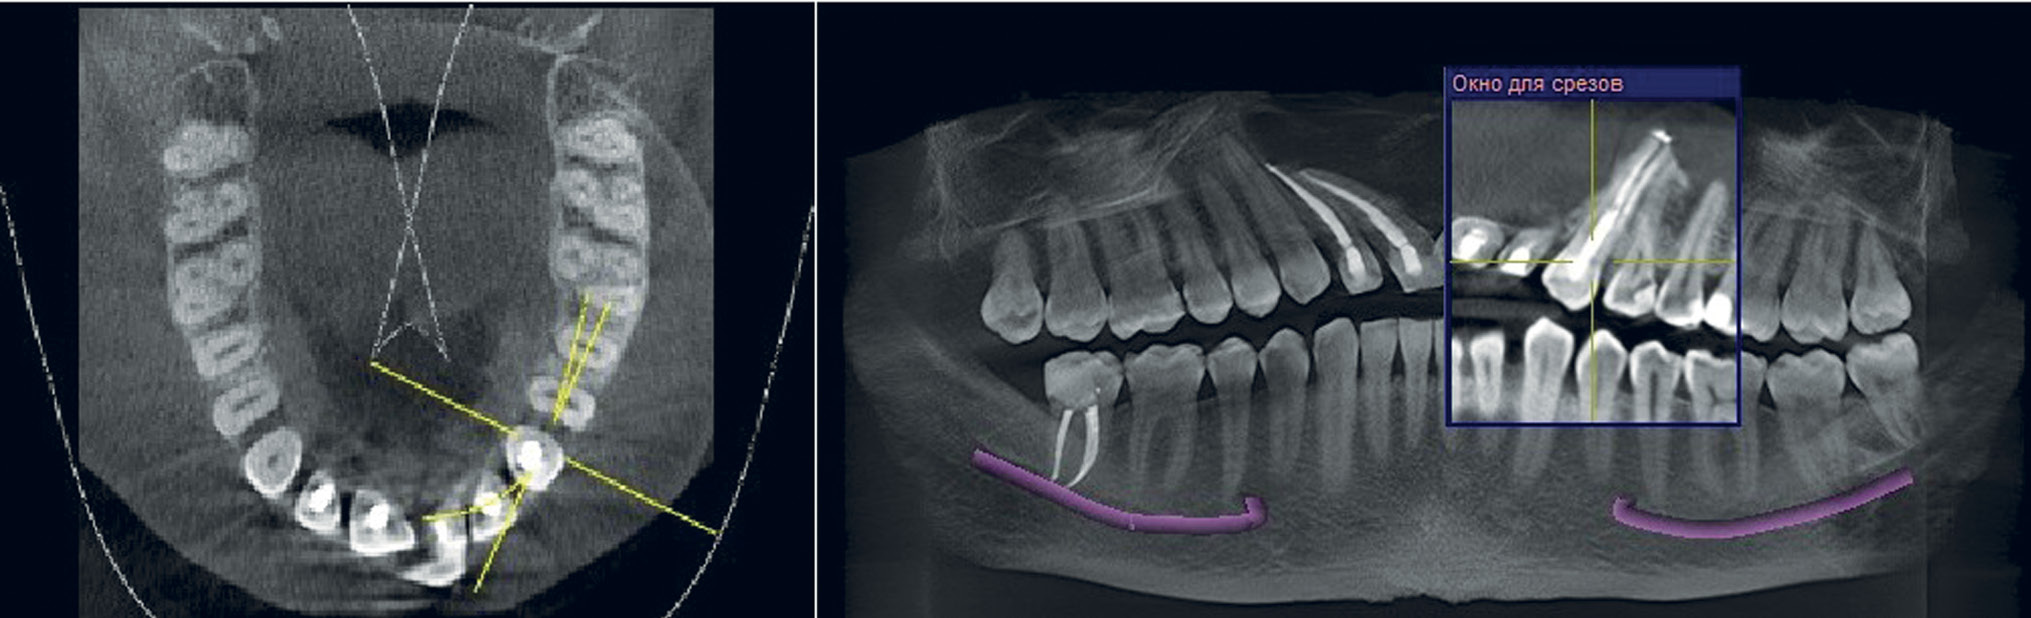

На конусно-лучевой компьютерной томограмме определяется очаг деструкции костной ткани округлой формы с четко ограниченными контурами, размерами 45,46×22,5×39,7 мм (рис. 1). Сверхкомплектный зуб располагается в полости очага деструкции верхней челюсти, частично оттесняя передненижнюю стенку левого верхнечелюстного синуса и нижнюю носовую раковину на 12 мм относительно нижней носовой раковины с противоположной стороны.

Рис. 1. Пациент Д., 33 года: данные конусно-лучевой компьютерной томографии на первичном приеме